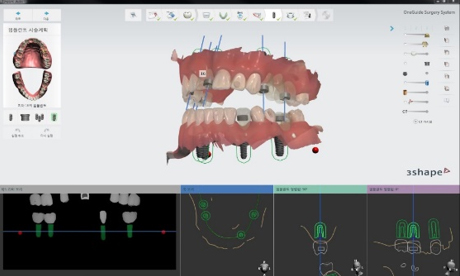

3D 디지털 모의수술을 통한

임플란트 과정을 미리보다3D CT 분석을 통한 검진 결과를 바탕으로 환자 맞춤형 가이드를 미리 제작합니다. 이후 3D 컴퓨터 모의수술을 통해 경로를 결정하고 소량 절개 시술로 잇몸 손상과 통증을 줄입니다. 오차는 줄이고 정확성은 높힌 디지털 임플란트 입니다.

디지털 임플란트의 특별함

골조직, 신경위치 자세히 분석 가능

최적의 임플란트 위치 선정 가능

빠르고 편리한 진료 과정

출혈, 통증, 붓기가 적은 최소 절개 시술로 빠른 회복